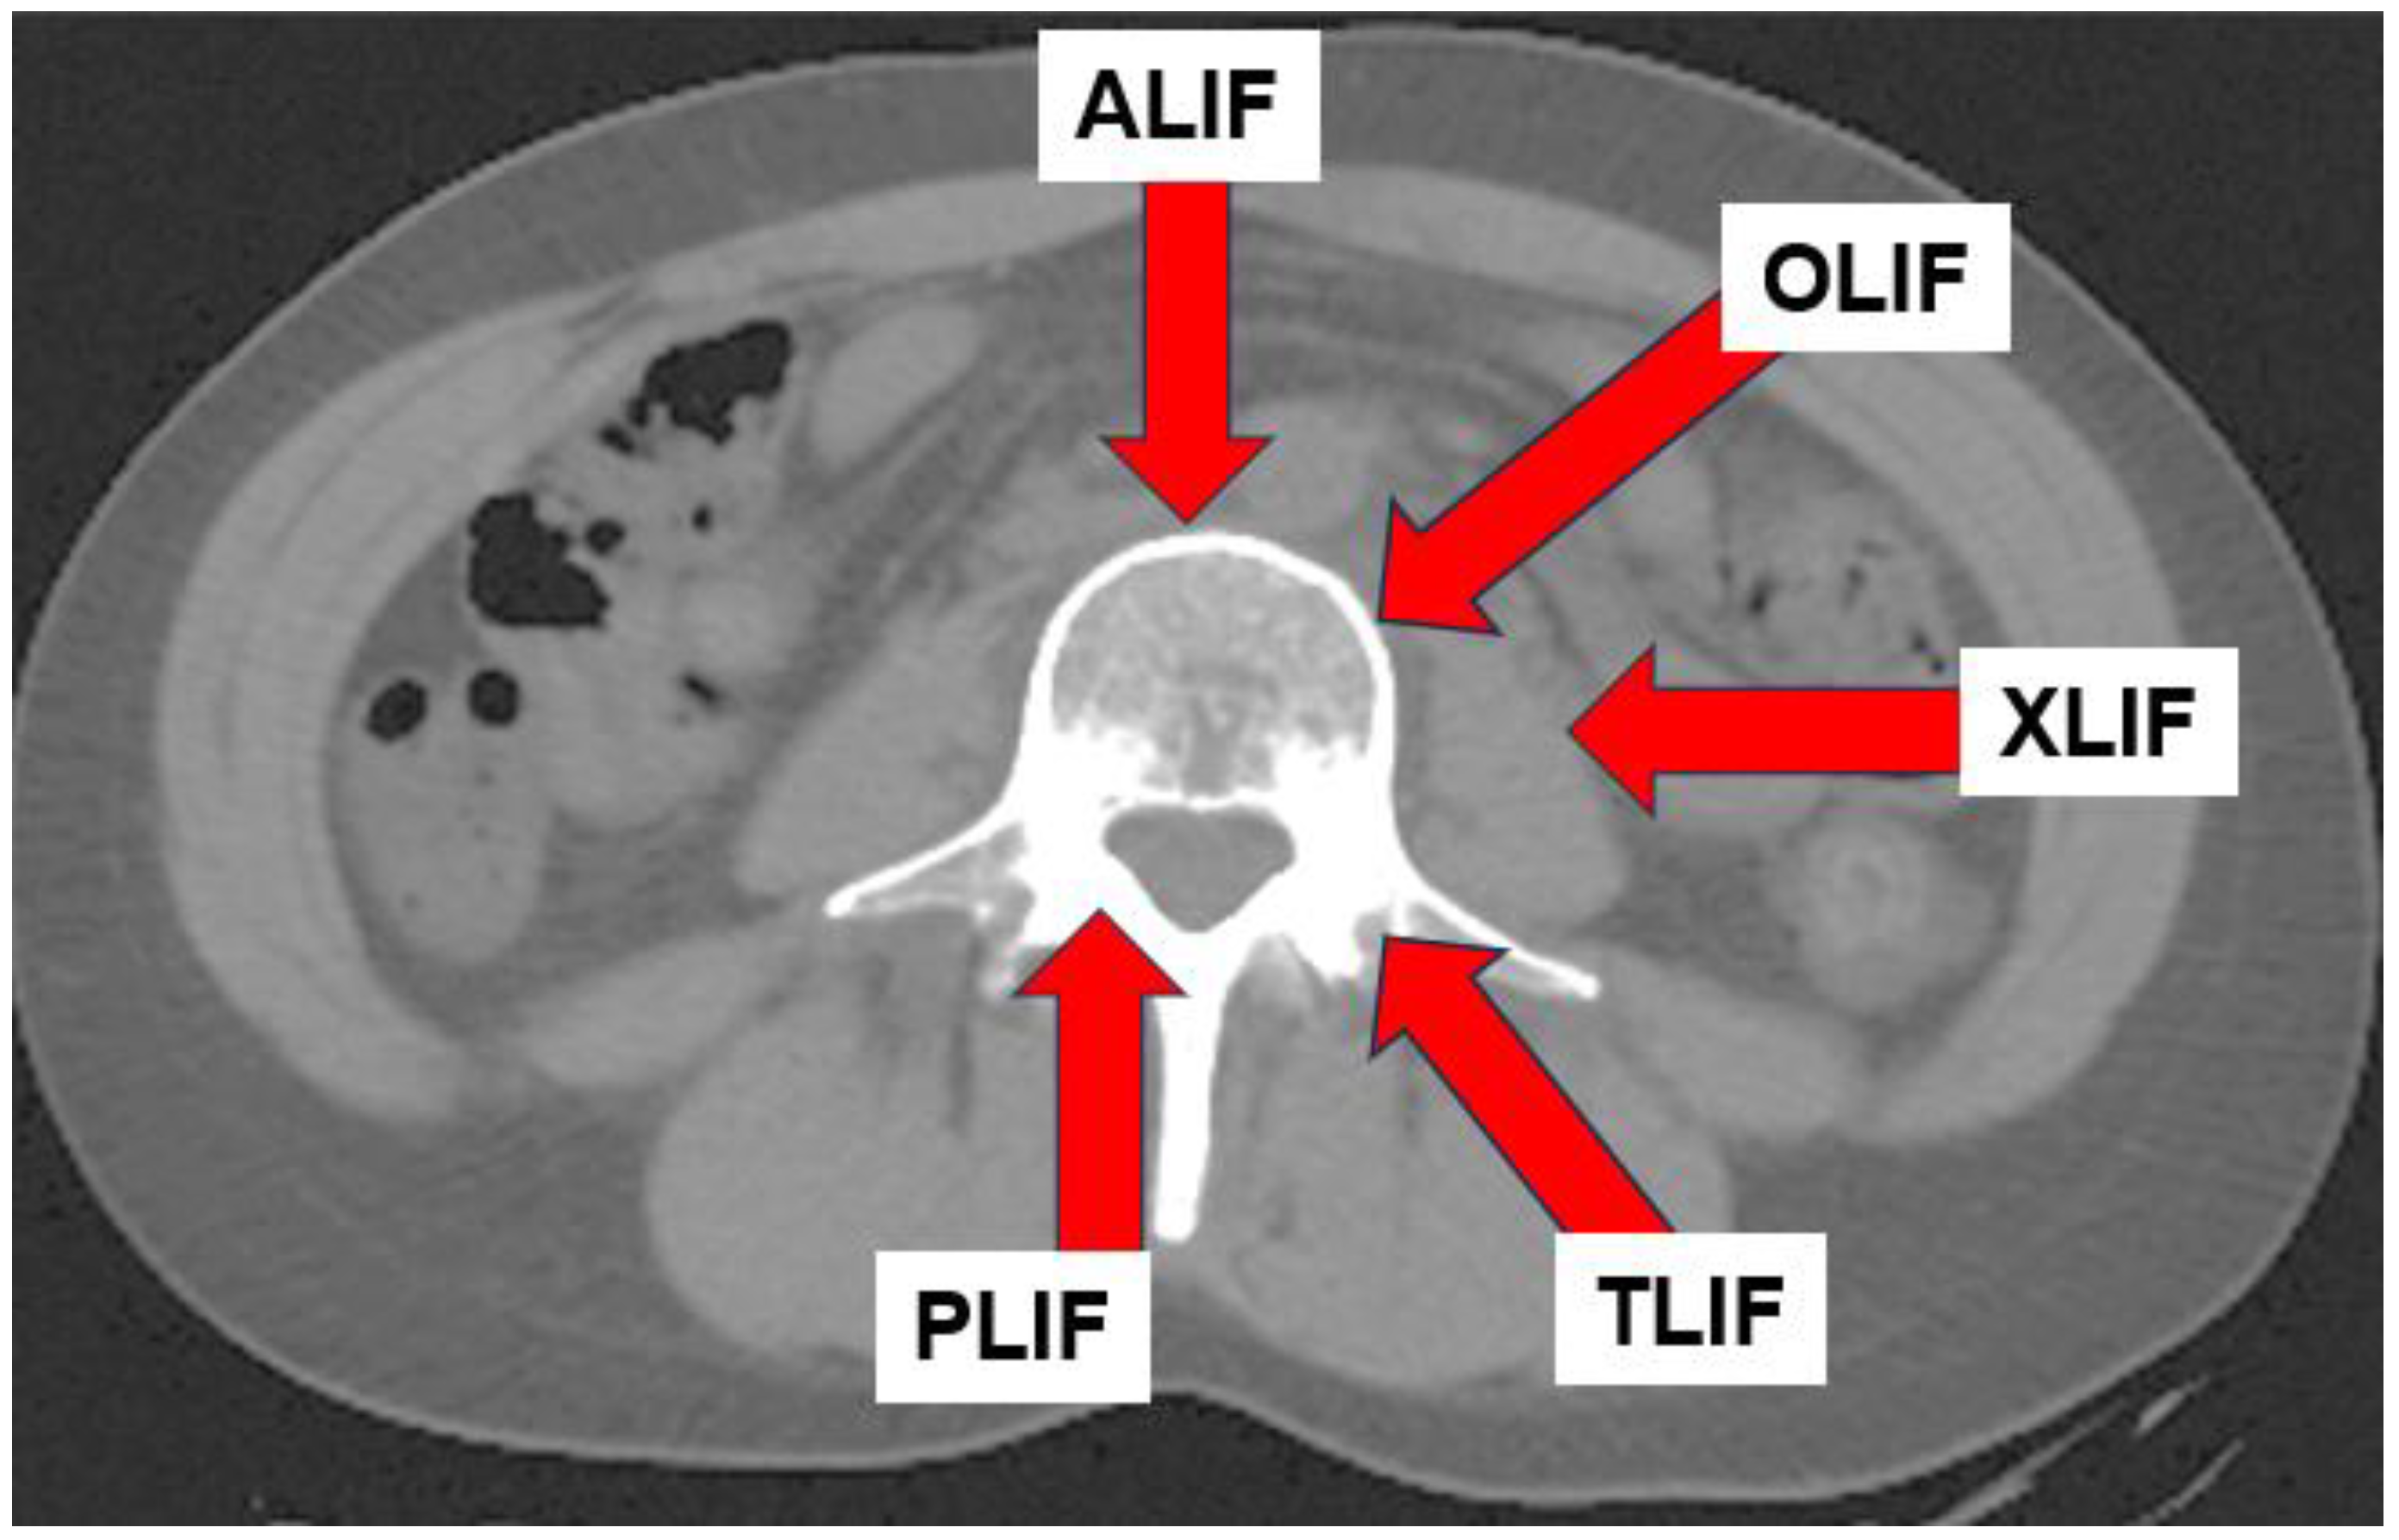

- Mobbs, R.J.; Phan, K.; Malham, G.; Seex, K.; Rao, P.J. Lumbar interbody fusion: Techniques, indications and comparison of interbody fusion options including PLIF, TLIF, MI-TLIF, OLIF/ATP, LLIF and ALIF. J. Spine Surg. 2015, 1, 2–18. [Google Scholar] [CrossRef] [PubMed] [PubMed Central]